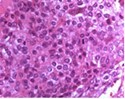

Upon microscopy, tumefaction is significantly cellular and composed of sheets of spherical to polyhedral chondroblastic cells imbued with abundant, eosinophilic cytoplasm and well demarcated cellular perimeter. Intracytoplasmic glycogen granules are evident. Nuclei appear elliptical, hyper-lobulated and demonstrate nuclear grooves. Nuclear atypia appears insignificant 1, 2.

Focal aggregates of spindle-shaped cells may be enunciated. Peri-cellular zones of ‘lace-like’ or ‘chicken wire’ calcification appear intermingled with degenerative chondroblasts. Eosinophilic foci of chondroid matrix are invariably discerned 1, 2.

Focal mitotic activity, necrosis and osteoclast-like giant cells may be commingled with cellular zones. Besides, aneurysmal bone cyst-like modifications are commonly observed 1, 2.

Figure 1.Chondroblastoma demonstrating round to oval chondroblastic cells with abundant, eosinophilic cytoplasm and vesicular grooved nuclei encompassed within a myxochondroid matrix5.

Figure 2.Chondroblastoma delineating aggregates of polyhedral chondroblastic cells with angulated, abundant, eosinophilic cytoplasm and vesicular nuclei enmeshed within a chondomyxomatous matrix6.